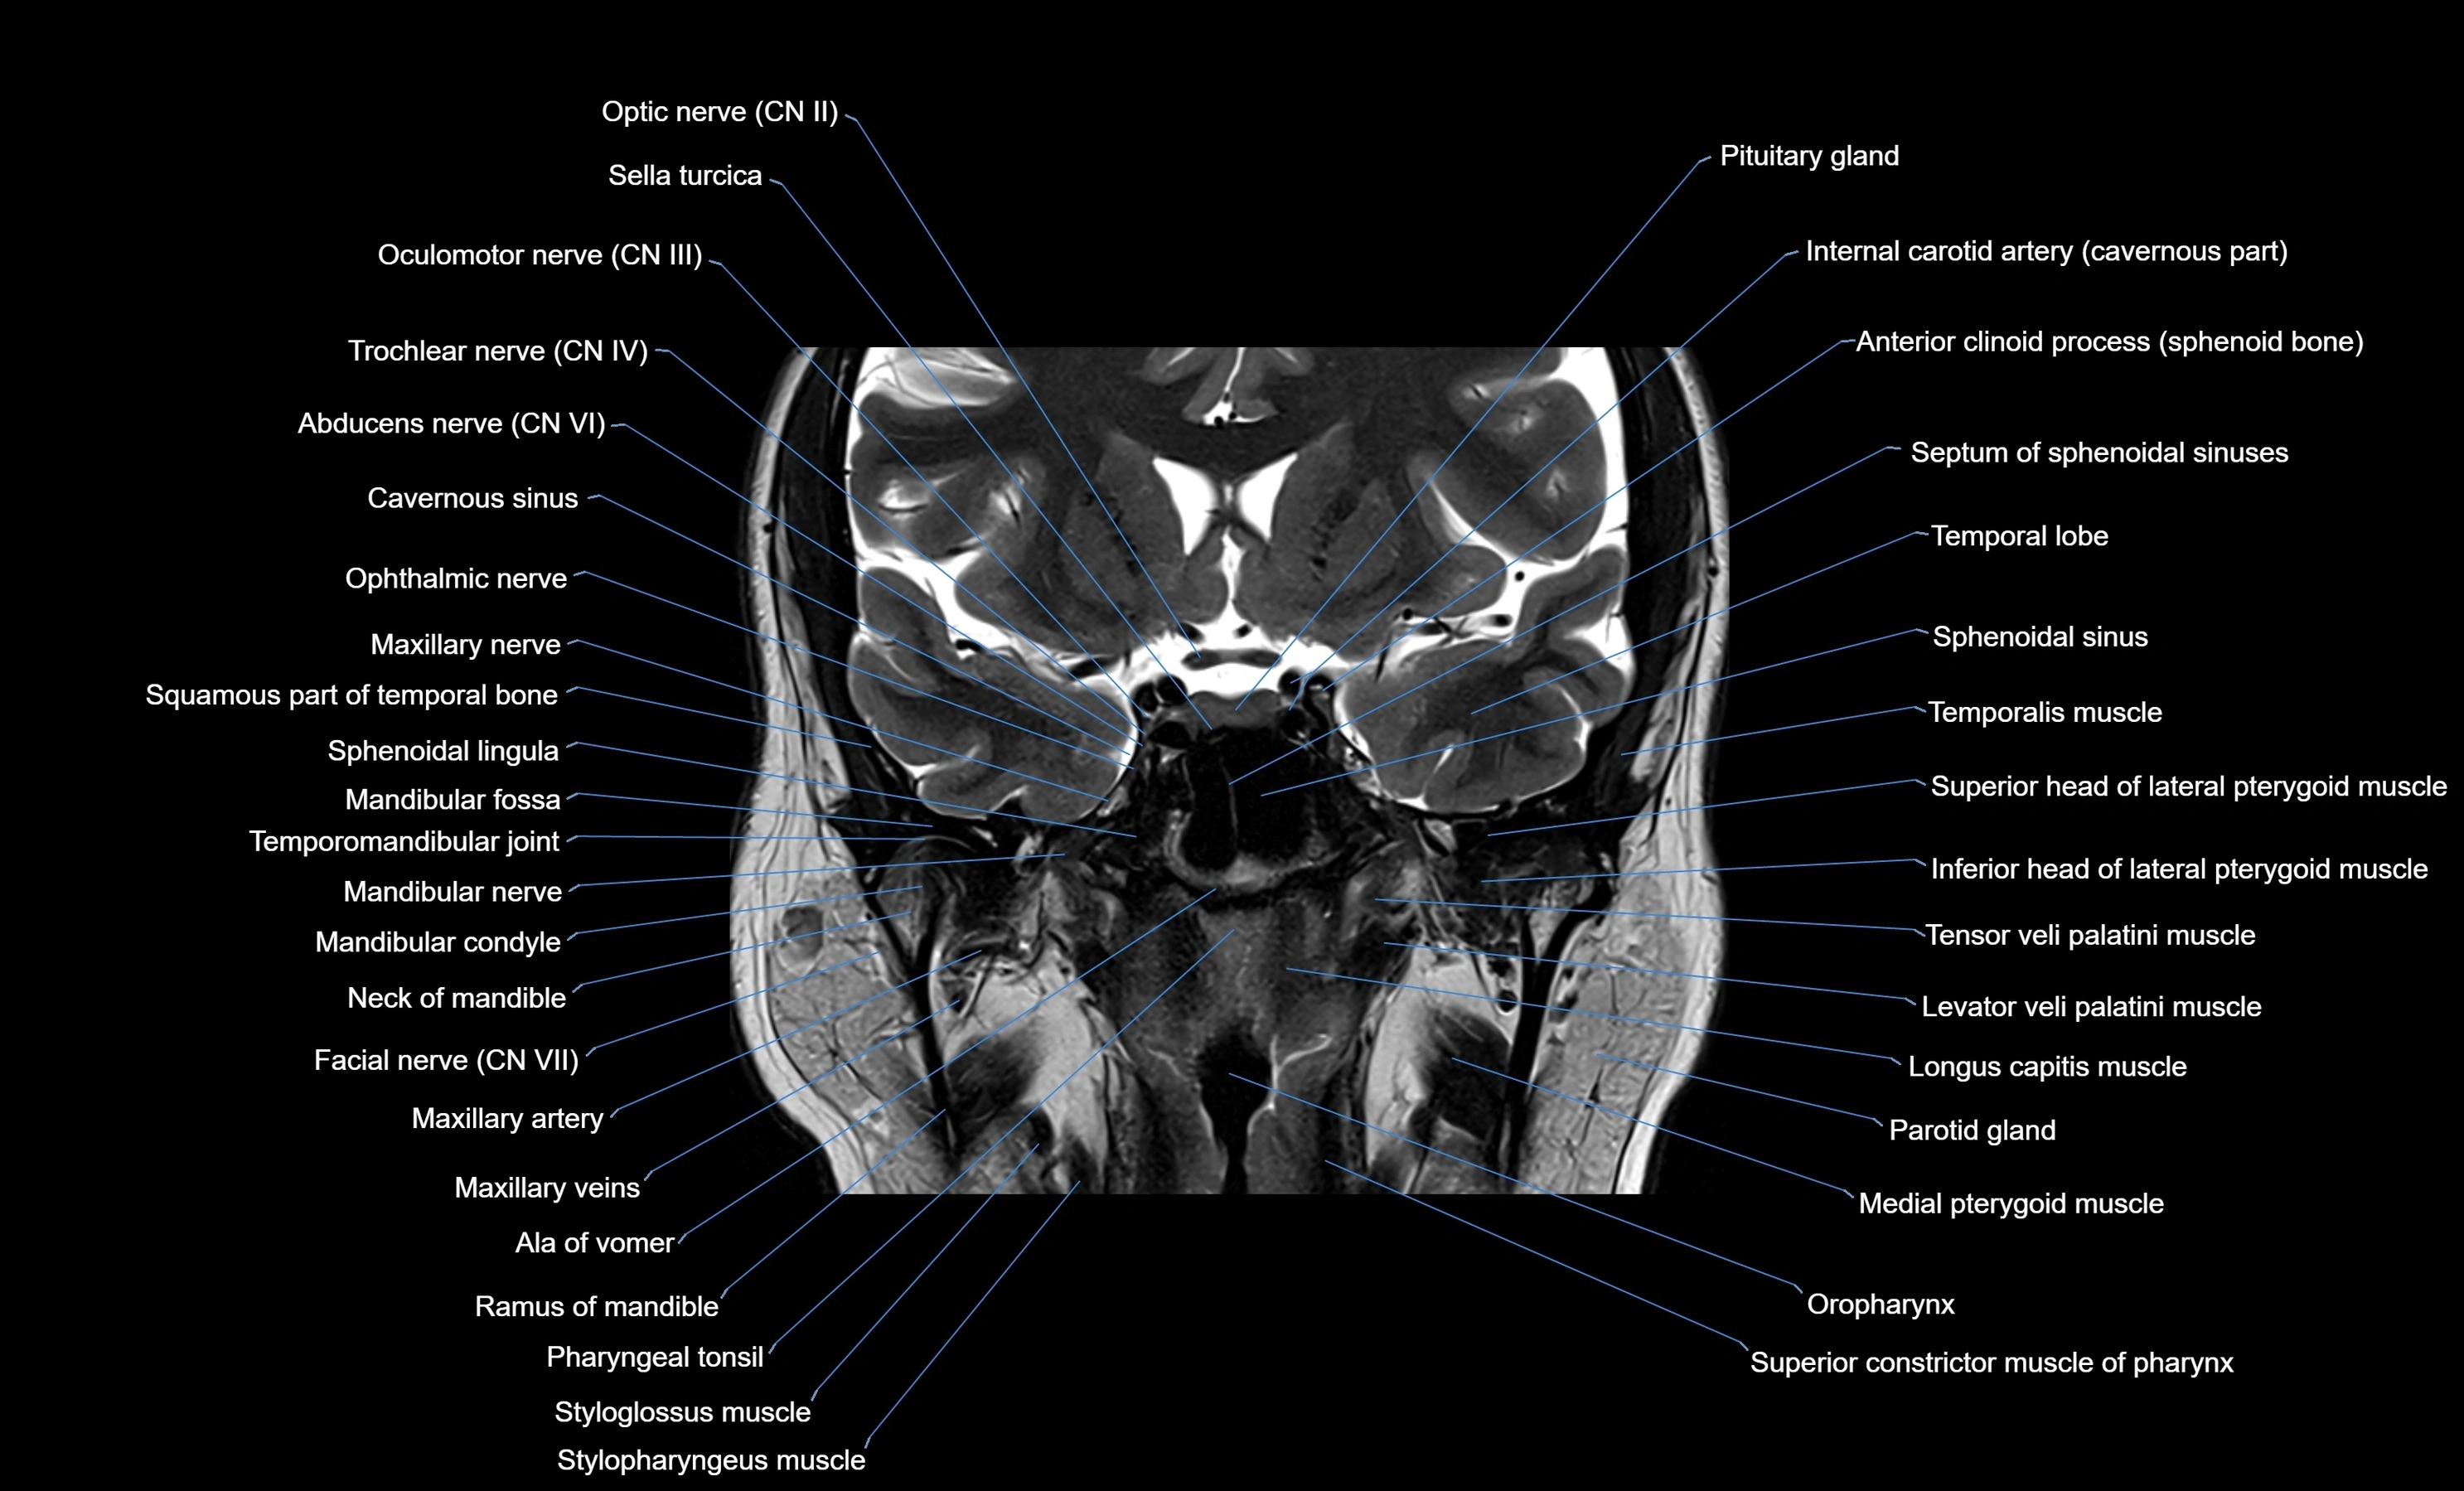

MRI images